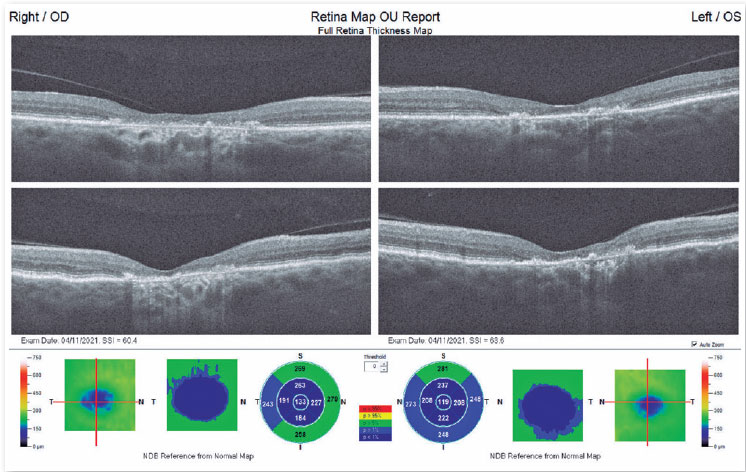

On optical coherence tomography (Figure 3), both eyes presented a vitreoretinal interface with an area of posterior vitreous detachment (PVD), pathologically increased foveal depression, neurosensory retina with loss of integrity and parallelism of the inner and outer retinal layers, atrophy of the associated outer retinal layers, ERP-BRUCH complex with areas of defects and deposits, choroid with thickness, reflectivity, and vascular layers within normal patterns.